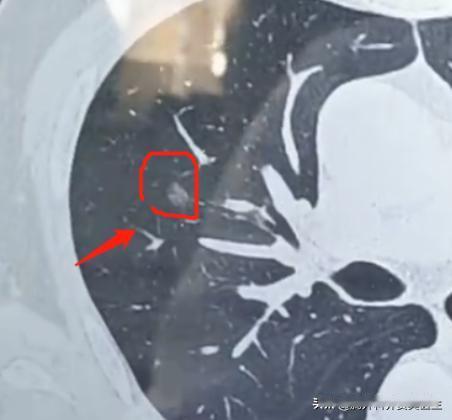

8mm肺结节手术后,是原位癌或微浸润癌,其他检查正常,但肿瘤标志物升高!是不是应该吃靶向药? 首先您不用太紧张!像这种8mm的原位癌或微浸润癌,手术切干净后一般是不需要再做其他治疗的,包括靶向药。 哪怕基因检测有突变,现在也不建议急着用药。 肿瘤标志物这个东西,其实没那么准。它升高不一定代表复发,很多其他情况也会影响: 1、手术本身的影响:刚做完手术那段时间,身体还在恢复,指标高点很正常; 2、炎症感染:最近要是感冒发烧了,或者哪里有炎症,指标也会上升; 3、身体状态:熬夜、劳累、压力大,都可能导致指标波动; 4、药物影响:有些中药、保健品也会干扰检测结果。我就遇到过几个病人,停了中药指标就正常了。 所以,现在其他检查都正常,光这一个指标高点不用太担心。 建议先观察1-2个月再复查,这段时间注意休息,别太累,如果有在吃中药或保健品建议停一停,如果有感冒发烧及时治疗。 需要警惕的是这2种情况: 1、肿瘤标志物特别高,超过正常值的两三倍以上; 2、肿瘤标志物持续升高,不断上升。[作揖][玫瑰]